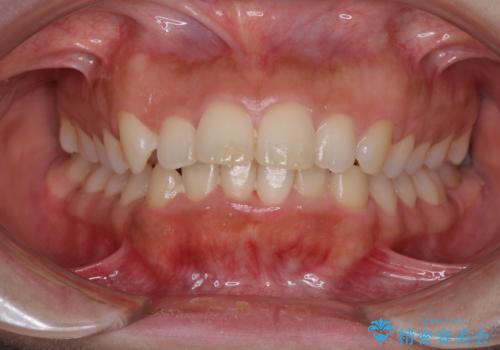

- 口元の突出感と口の閉じにくさを気にして来院された患者様です。

上下左右の小臼歯4本を抜歯し、ワイヤー装置にて口元を引っ込めるよう矯正治療を行うこととしました。

上下顎ともに前突しており、特に上顎は著しい突出感でした。

また、下顎歯列には左右差があり、非対称な抜歯が必要と判断されたため、治療は困難なものとなりました。